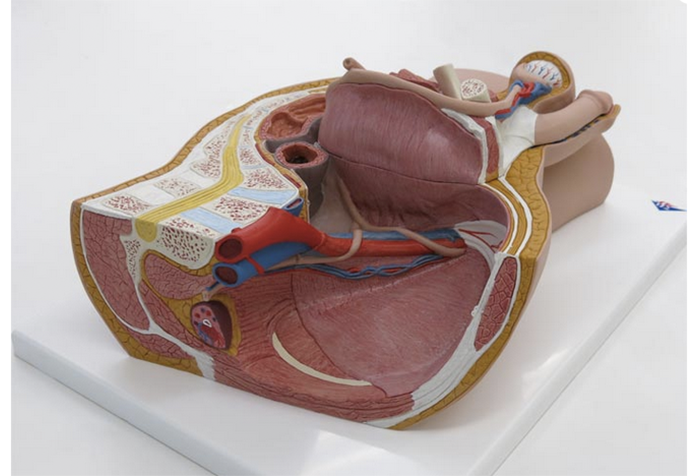

骨盤臓器脱 亀田メディカルセンター ウロギネ 女性排尿機能センター

女性骨盤 内臓 骨盤底筋付 6分解モデル 日本スリービー サイエンティフィック

女性骨盤 内臓 骨盤底筋付 6分解モデル 日本スリービー サイエンティフィック